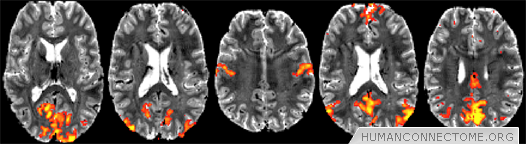

Figure 2: Preliminary resting-fMRI independent component analysis (ICA) results from 7T at 1.5mm isotropic resolution, single-subject data. 50-dimensional ICA shows exquisite cortical detail in several resting networks: low-level visual, higher visual, sensorimotor, primary default mode network (DMN) and secondary DMN.